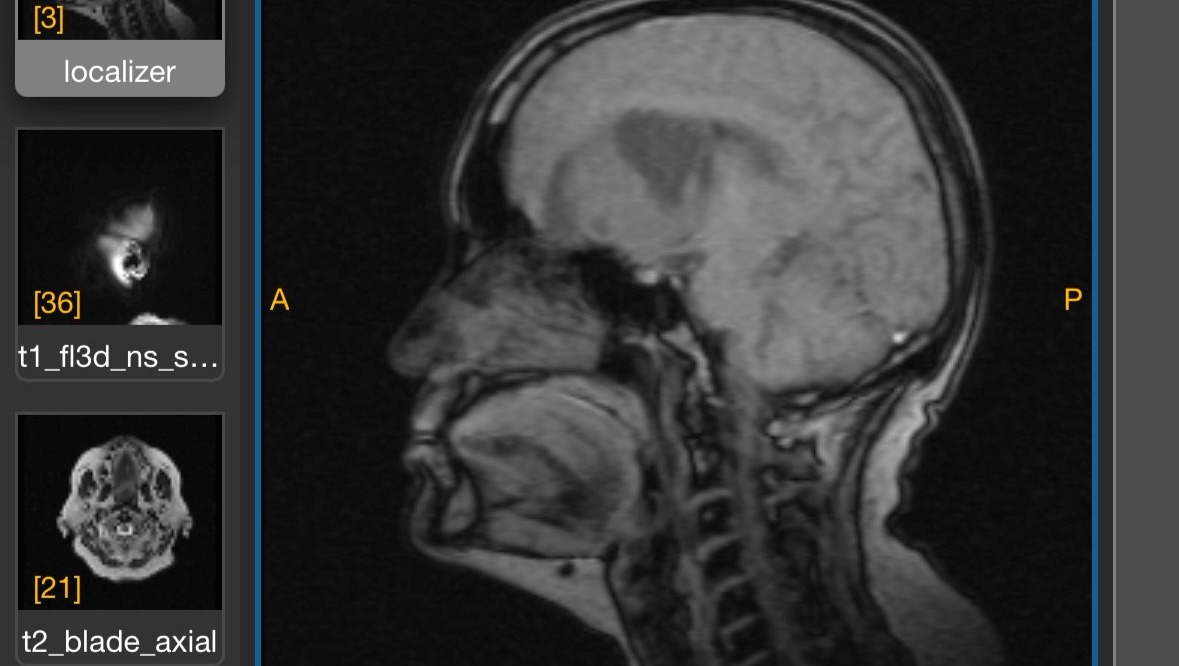

Edith Zambrano necesita someterse a una cirugía craneal de urgencia debido a un hallazgo en el area FRONTOPARIETAL diagnosticado como PROCESO MALFORMATIVO ANEURISMATICOS ARTERIOVENOSOS (TUMOR BENIGNO), lo cual actualmente esta causando pérdida de memoria, trastornos en el lenguaje, locomoción y control de esfínter , que conlleva a una intervención de urgencia para evitar daños progresivos, siendo vital para salvar su vida y garantizar su recuperación.

Edith Zambrano needs to undergo emergency cranial surgery due to a finding in the FRONTOPARIETAL area diagnosed as ARTERIOVENOUS ANEURYSMAL PROCESS (BENIGN TUMOR), which is currently causing memory loss, language disorders, locomotion and sphincter control, which leads to an emergency intervention to avoid progressive damage, being vital to save her life and guarantee her recovery.